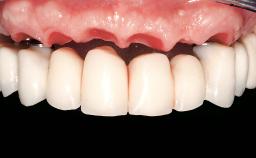

Conventional Loading of Eight Implants in the Maxilla and Final Restoration with a Full-Arch Gold-Ceramic FDP

| Prosthesis Type | FDP |